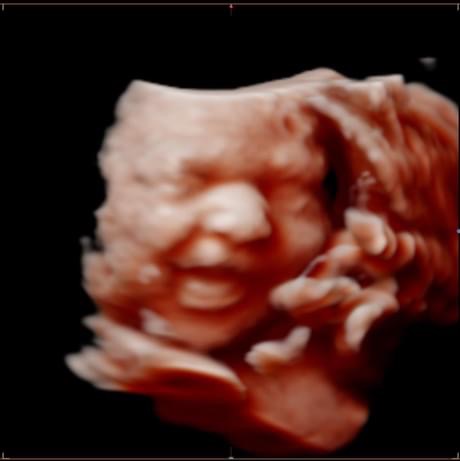

All photos are from our equipment and are of our actual clients.